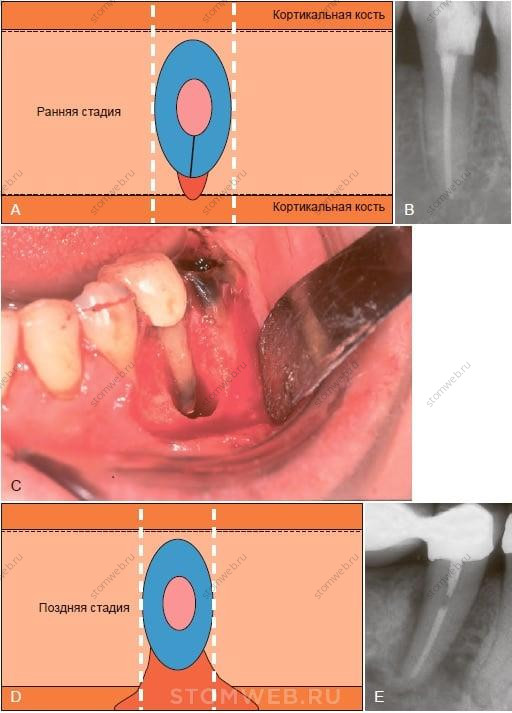

На ранней стадии вертикального перелома корня может появиться боль или дискомфорт с пораженной стороны зуба. В частности, чувствительность и дискомфорт могут появляться при жевании, боль чаще тупая, в противоположность острой боли, типичной при трещине бугра или зуба с живой пульпой. При прогрессировании поражения и сопутствующей инфекции часто возникает отечность и может появиться свищевой ход, локализованный более коронально, чем свищевой ход при хроническом апикальном абсцессе (Рис. 21-12). Все эти признаки затрудняют дифференциальную диагностику с отрицательной динамикой эндодонтического лечения. На ранних стадиях рентгенологические проявления редки, так как (1) пломбировочный материал в корневом канале загораживает трещину (Рис. 21-13, А), и (2) изображение корня накладывается на участок деструкции костной ткани (который все еще имеет небольшие размеры мезио-дистально)

РИС. 21-14 Сравнение рентгенографии очага деструкции кости в связи с вертикальным переломом корня на ранней и на поздней стадиях. На ранней стадии очаг деструкции кости (красный) вряд ли может быть обнаружен на прицельной рентгенограмме, поскольку перекрывается изображением корня (А,В). На более поздней стадии , когда очаг деструкции распространился до кортикальной пластинки (С), и выступает за пределы силуэта корня (С,D) выглядя при этом как участок просветления вдоль корня (D).